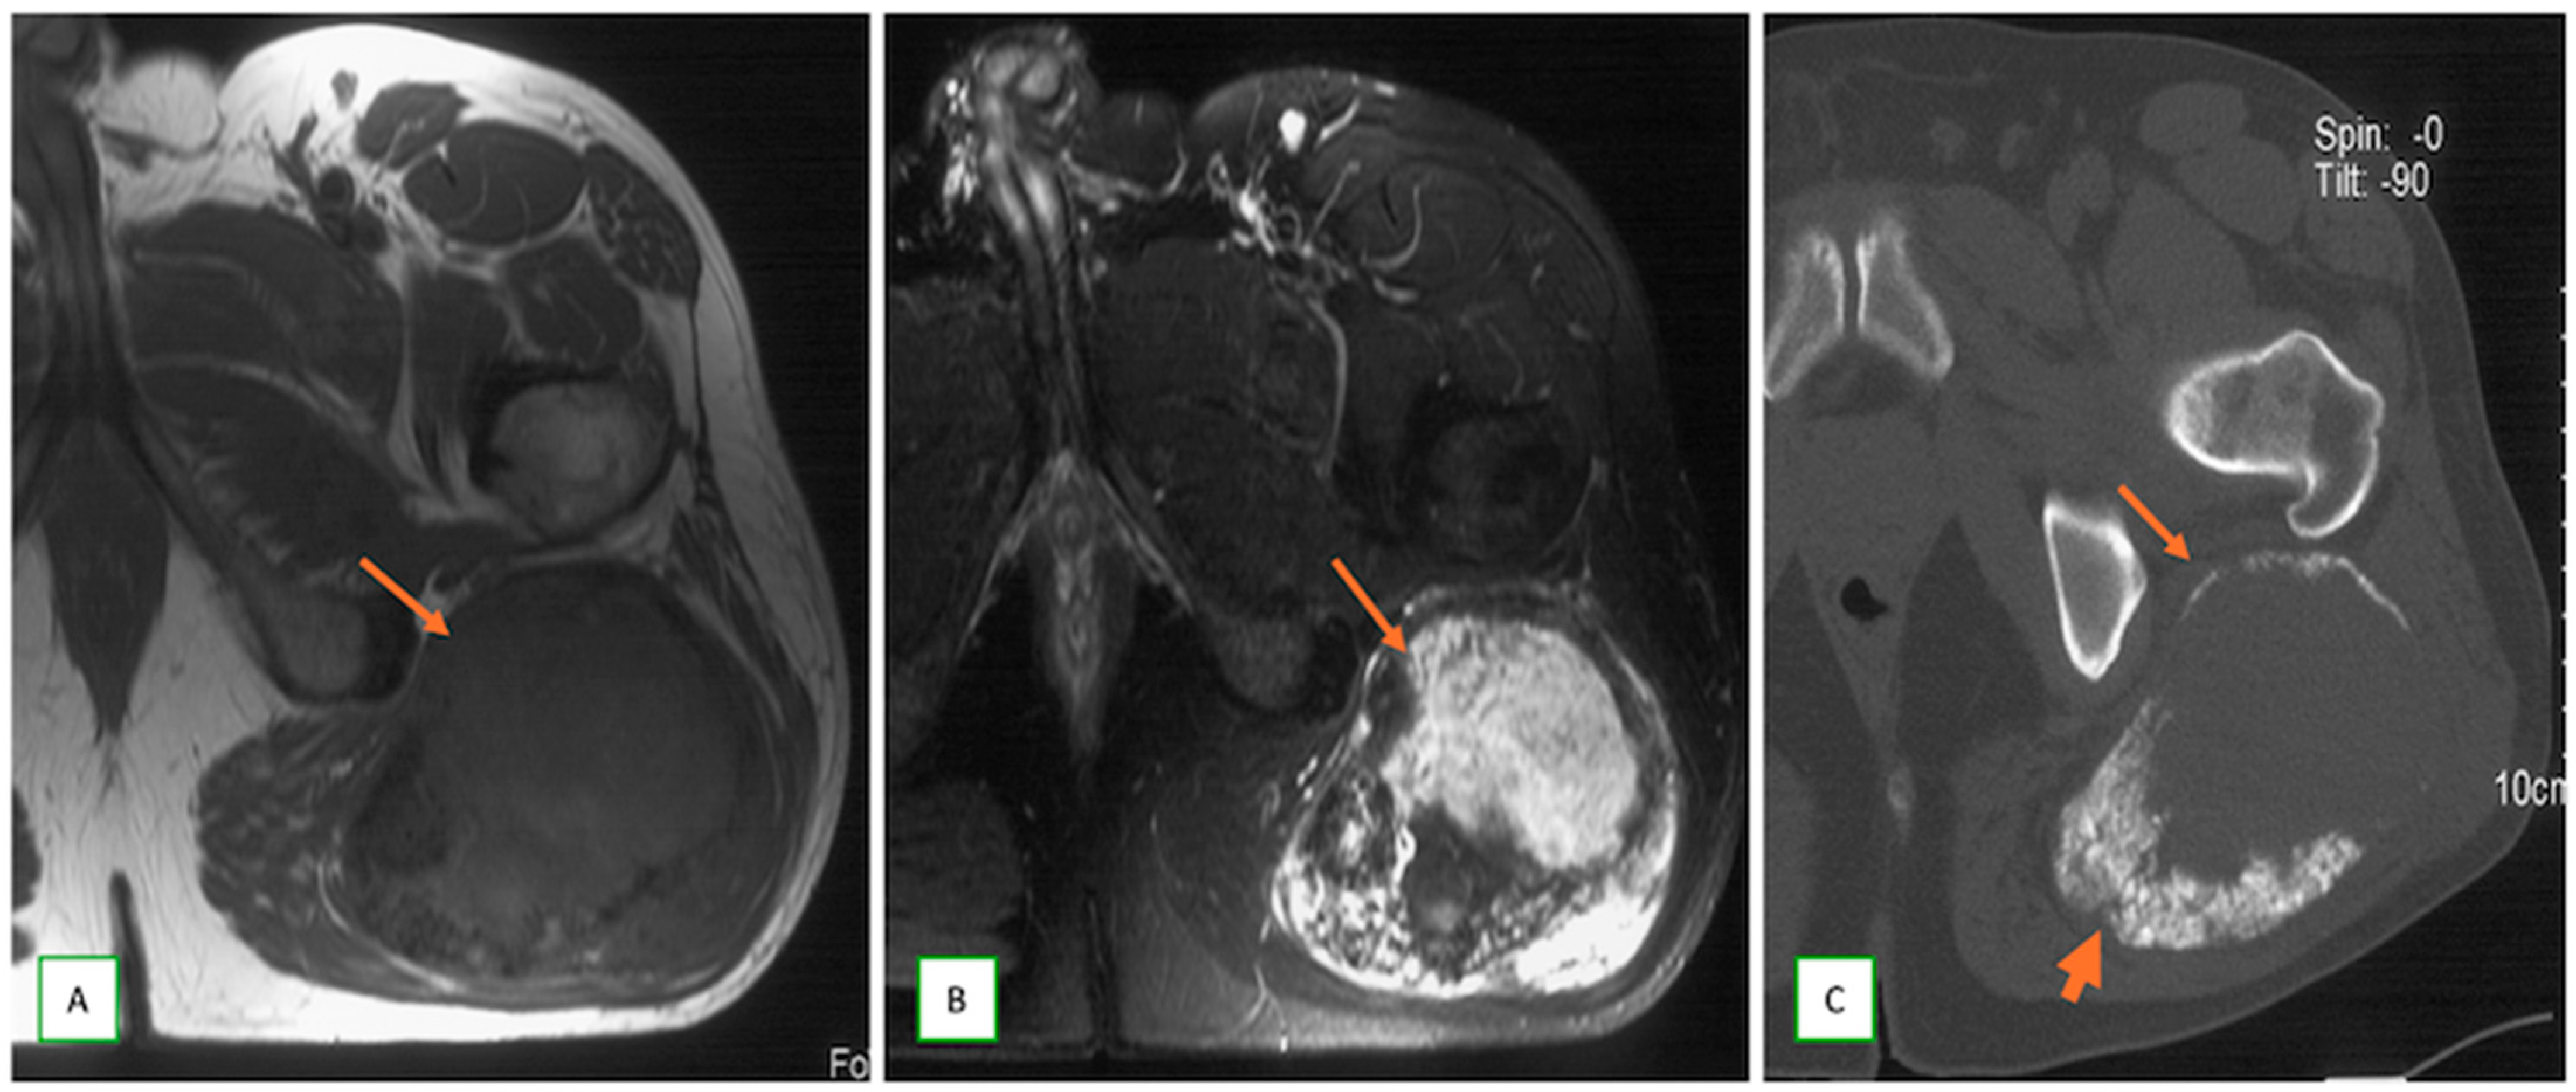

- Primary Sarcomas: Soft-tissue sarcomas are uncommon, accounting for just over 1% of adult malignancies. Synovial sarcoma, clear cell sarcoma, and epithelioid sarcomas are known to involve peripheral nerves. CT/MR reveals a large soft tissue mass with areas of necrosis or calcification and heterogeneous contrast enhancement. F-18 FDG uptake is useful for both tumor staging and treatment assessment (Figure 26, Figure 27 and Figure 28).